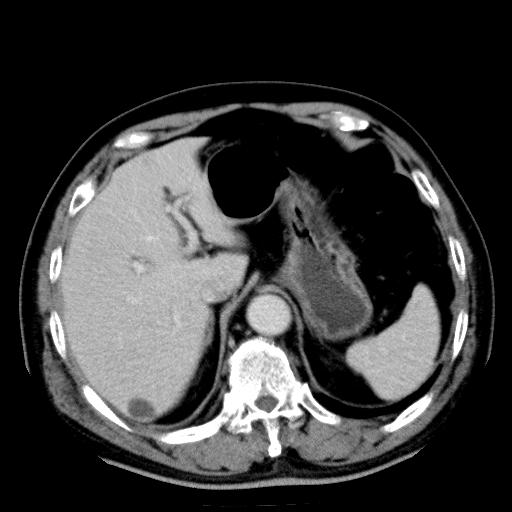

以下是引用zhctwbh在2008-8-23 14:20:00的发言:[br]囊肿合并出血

以下是引用zjb在2008-8-23 16:41:00的发言:[br]囊肿并出血可能性大。